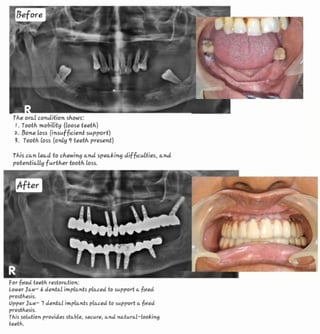

Full mouth implant cases in affordable treatment option

FIX TEETH WITH DENTAL IMPLANTS

Revolutionize Your Smile with Dental Implant